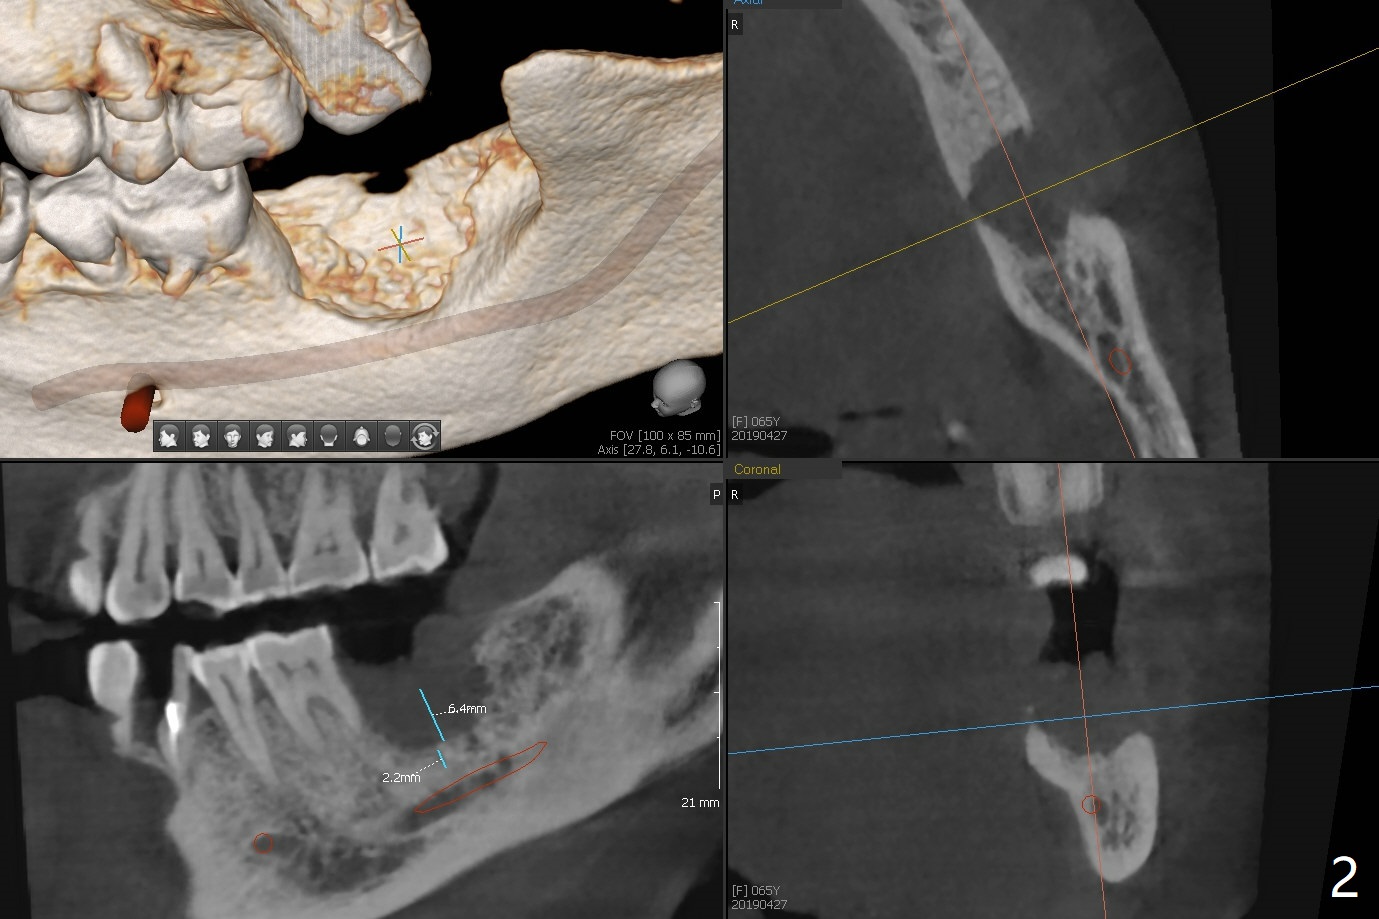

A 65-year-old woman seeks treatment after exfoliation of #18 (Fig.1). It appears important to have implants at #18 and 31 for longevity of restoration or implants at fractured teeth (*). The implant restoration at #31 will have challenge because of the supraeruption of the opposing tooth (arrow). The socket at #18 is large, shallow (Fig.2) and not healing. After debridement, bone graft will be placed, followed by 6 month membrane. Space maintenance will be installed for periodontal dressing stability. Prepare PRF if the vein is large enough.

To increase bone density, use a large 8/9 mm trephine bur to harvest ramus block graft on the right with depth of 3 mm (Fig.4 red circle) after SRP in the lower arch and transfer to #18 socket (Fig.3 pink), fixed in place with a screw (probably 6 or 8 mm tenting one, yellow) after filling the socket with particulate bone graft (Vanilla, white circle).

Steven: Wait couple of months and take another CT ,check again maybe need another grafting. Another approach is to alter the trajectory of the implant bypass the IAN and use the angled abutment to restore the case.